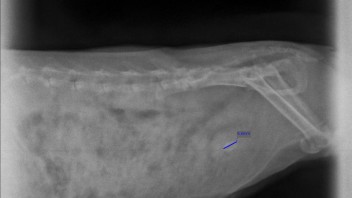

Unser Flash (ca. 4,5 Jahre, männlich) hat einen Blasenstein (ca. 6-7 mm groß) und leider dazu eine mittelgradige Mitralklappeninsuffizienz. Den Stein haben wir erst versucht aufzulösen mit Rodicare Uro + UTI KN Tabletten. Leider hat das nicht den gewünschten Effekt gebracht. Flash hat immer wieder mal Probleme mit der Blase, zwar keine schlimme Entzündung, aber immer mal Reizungen und Schmerzen beim Urin absetzten. Mit Metacam haben wir das aber immer gut in den Griff bekommen. Die anderen Medikamente bekommt er seit der Diagnose dauerhaft.

Flash hat die Tabletten 2 Wochen lang wie empfohlen bekommen, 2x2 Tabletten pro Tag (haben diese in Wasser gelöst und mit einer Spritze direkt ins Mäulchen gegeben.) Bereits nach einigen Tagen hat Flash vermehrt weiße Flecken im Gehege hinterlassen (Vlieshaltung). Dies haben wir als gutes Zeichen wahr genommen. Nach diesen 2 Wochen sind wir zur US Kontrolle zum Arzt gegangen, um zu schauen, ob es überhaupt in irgendeiner Weise eine Wirkung gibt. Beim US der Blase haben wir noch gut Schlamm/Gries in der Blase sehen können - ABER KEINEN STEIN!!! Sowohl der Arzt als auch wir waren baff :-) Er hat sich direkt nach dem Medikament erkundigt, da er es nicht kannte.